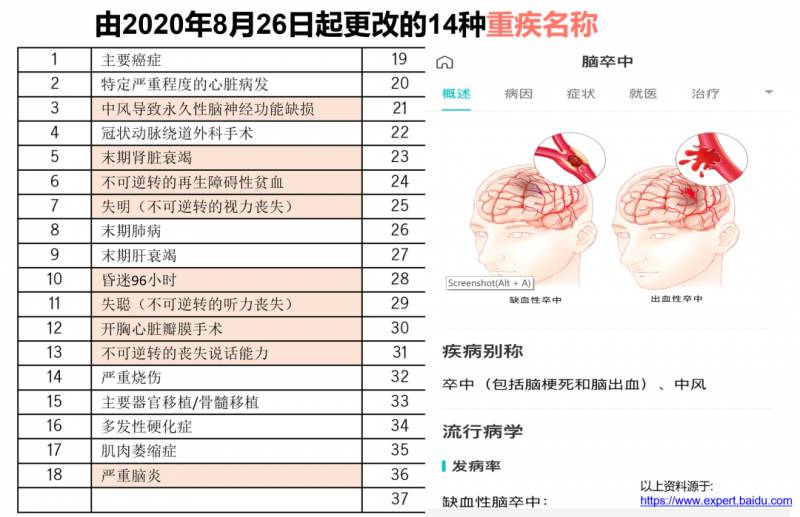

2020年8月26日开始,新加坡有21种重疾定义更改5。

重疾险标准进行了调整,比如失聪,考虑到医学技术进步可能让失聪的人恢复部分听觉,“失聪”也更明确定义为“不可逆转的失聪”。